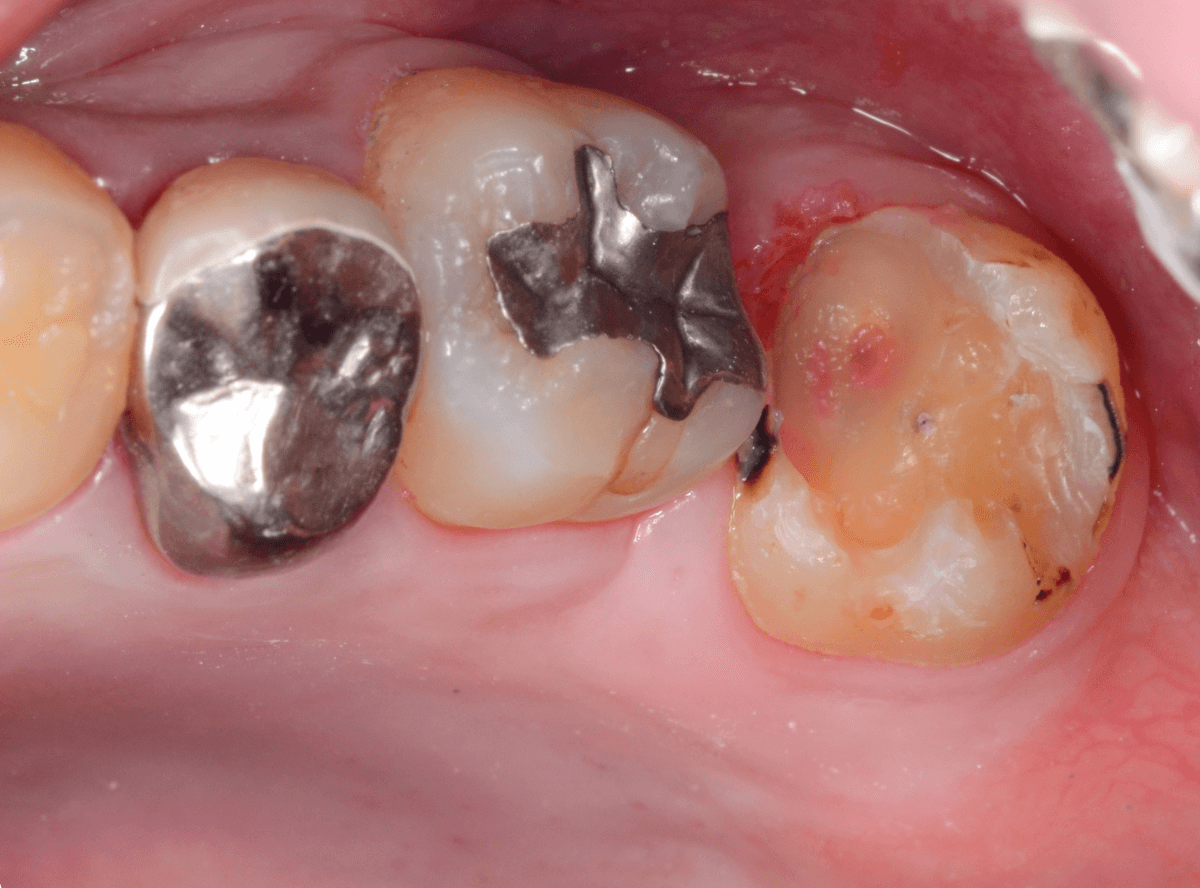

Case.12 検診で見つかった、インレーの下の深い虫歯

検診目的で来院された患者さんです。

特に気になるところもなかったですが、検査をすると、お口の中の色々な部分に虫歯が見つかりました。

その中の一か所、上の奥歯のインレーの下の虫歯です。

見た目だけでははっきりわかりませんでしたが、レントゲン写真で確認すると、インレーの下で虫歯になっているのがわかります。

インレーを除去して、治療を開始します。

ある程度、虫歯を除去したところで、う蝕検知液で確認します。

赤い部分が虫歯です。

やはり、レントゲン写真で確認した部分が深めの虫歯になっていたようです。

全ての虫歯を除去しました。

お薬をつめて痛みやしみが出ないか、しばらく経過観察しますが、おそらく大丈夫でしょう。

症状が出る前に、検診に来ていただいたことで最小限の治療で済みました。